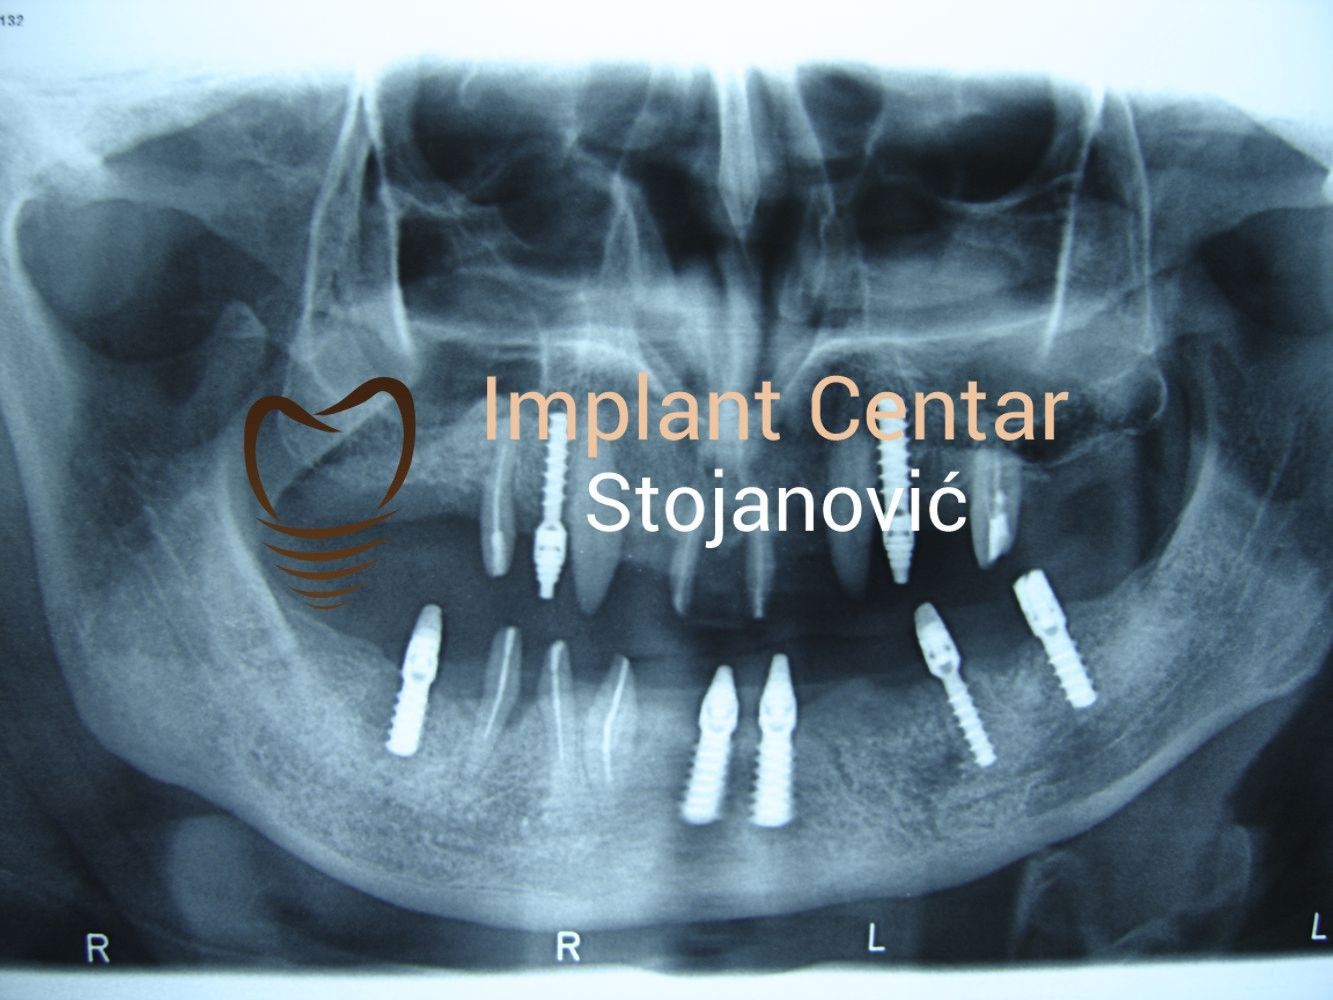

Pacijent 68g. iz Švajcarske. Zbog loših anatomskih uslova i izbegavanja sinus lift operacije, što bi produžilo ukupno trajanje rada do dve godine, odlućeno je uz dogovor sa pacijentom, a prema našem dugogodišnjem iskustvu, da se ugradi 10 implantata u gornju vilicu, od toga dva tuberopterigoidna implantata i 6 implantata u donju vilicu. Izrađeni su cirkonijumkeramički mostovi u gornjoj i donjoj vilici. U Švajcarskoj je pacijentu predložen All-on-4 kao rešenje njegove bezubosti u gornjoj vilici, ali on nije želeo da ponovo nosi protezu. Mi ne podržavamo concept All-On-4, jer 90 % slučajeva postoje uslovi za fiksne radove sa 6 do 8 implantata. Sa fiksnim radom pacijenti su prezadovoljni. All-on-4 je najčesće nametnuto rešenje od strane doktora, zbog lakšeg i jednostavnijeg načina rešavanja, prenoseći teret na pacijenta, koji će i dalje nositi protezu. Pacijent je zadovoljan i u pozitivnoj je komunikaciji sa nama.